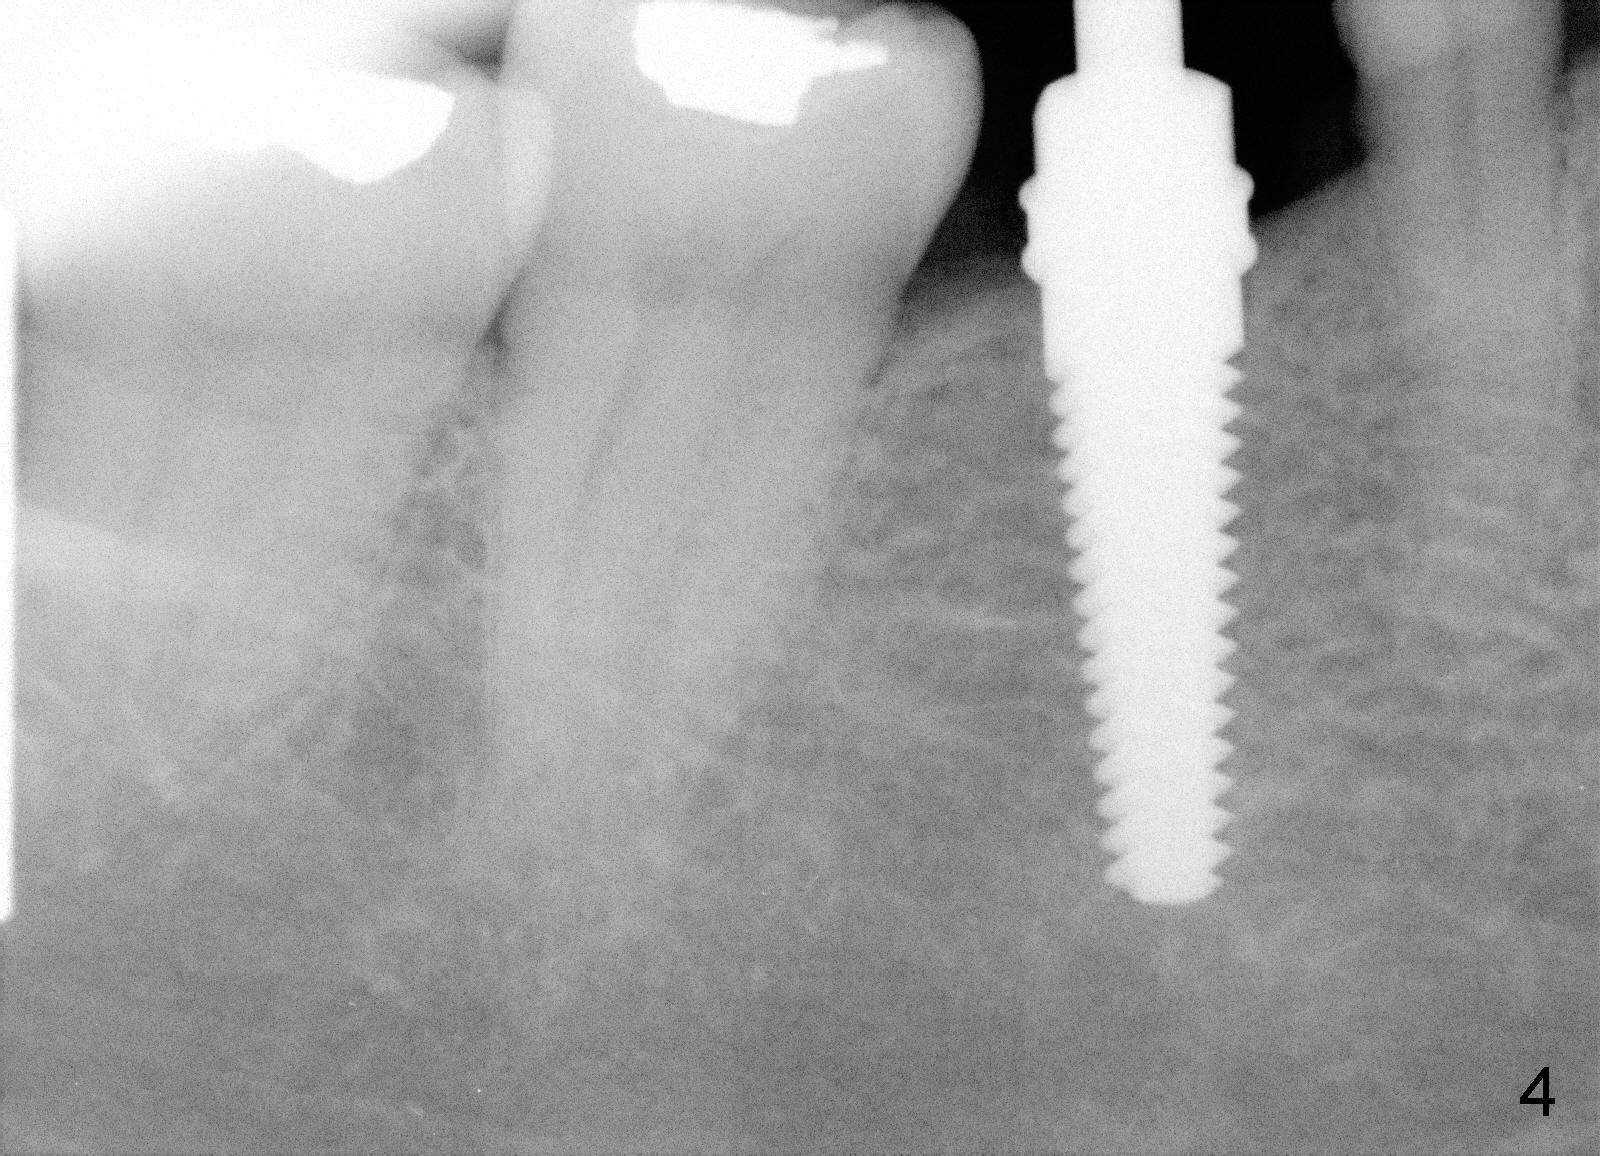

Due to unavailability of bone-level implant, a tissue-level implant is to be placed as a backup (Fig.1: 4.5x17 mm). Osteotomy is initiated with 1.5 mm pilot drill at depth of ~ 10 mm; the trajectory appears to be as good as expected (Fig.2). Osteotomy is gradually increased to 4.5x17 mm, followed by insertion of 4.5x17 mm tap (Fig.3,4). The ostetomy appears to be deviated lingual (Fig.5). When the tap is removed, the buccal plate appears to be thin (Fig.6). A tapered implant is placed (Fig.7).